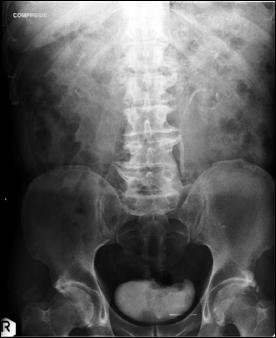

Diagnosticul diferential cu tuberculoza urogenitala

Vezica urinara are contururi greu delimitabile pe cistografie si pacientul are ureterohidronefroza bilaterala.

Figura 57. Vezica urinara mica |

Vezica urinara mica, scleroasa, cu rinichi drept unic chirurgical, uretero-hidronefroza gr I

Figura 59. Vezica urinara "crispata", cu ureterohidronefroza bilaterala. |